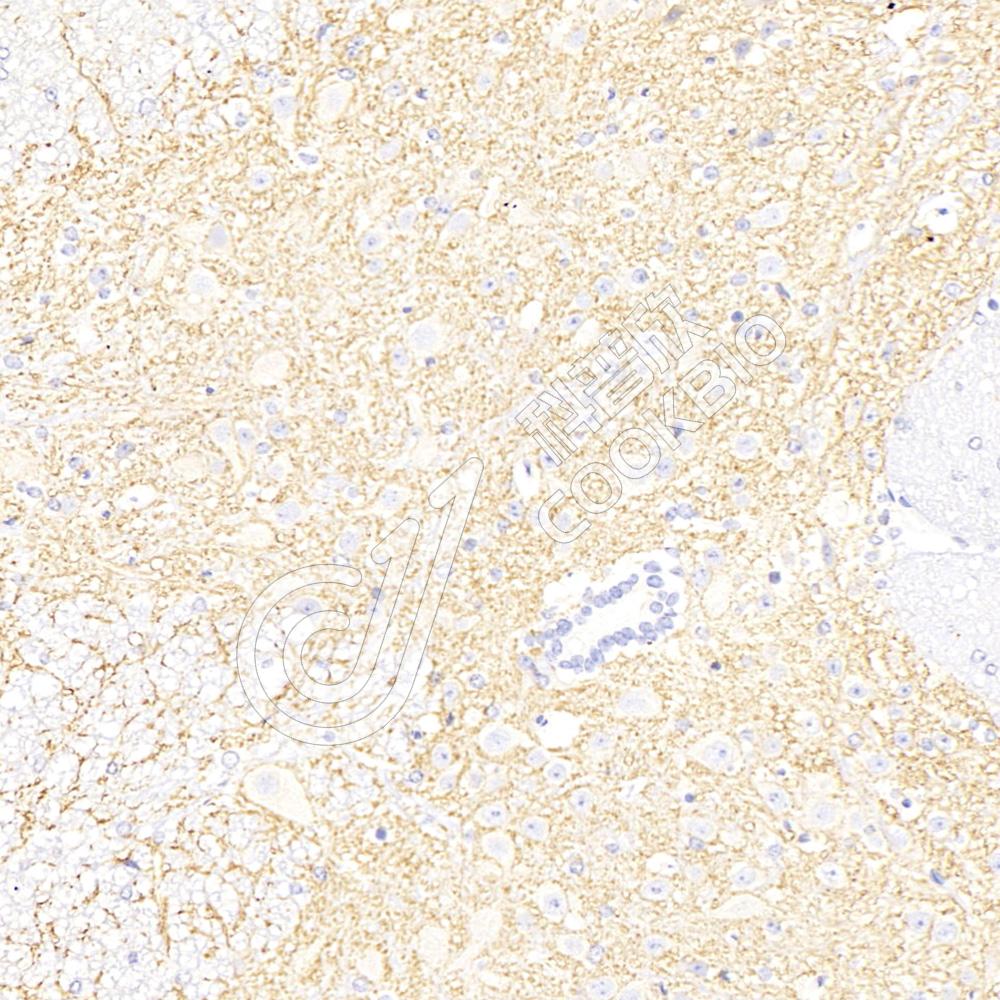

IHC检测NMDAR1蛋白(货号 K133432).

样品: 小鼠脑, 4%多聚甲醛 (货号KSG1101) 固定12-24小时.

抗原修复: 柠檬酸抗原修复液(干粉, pH 6.0) (KSG1201), 98℃, 20分钟.

—抗: 1: 300稀释, 4℃ 孵育过夜.

二抗: S-vision免疫组化多聚二抗(山羊抗兔),即用型 (货号KB3906), 室温孵育20分钟.